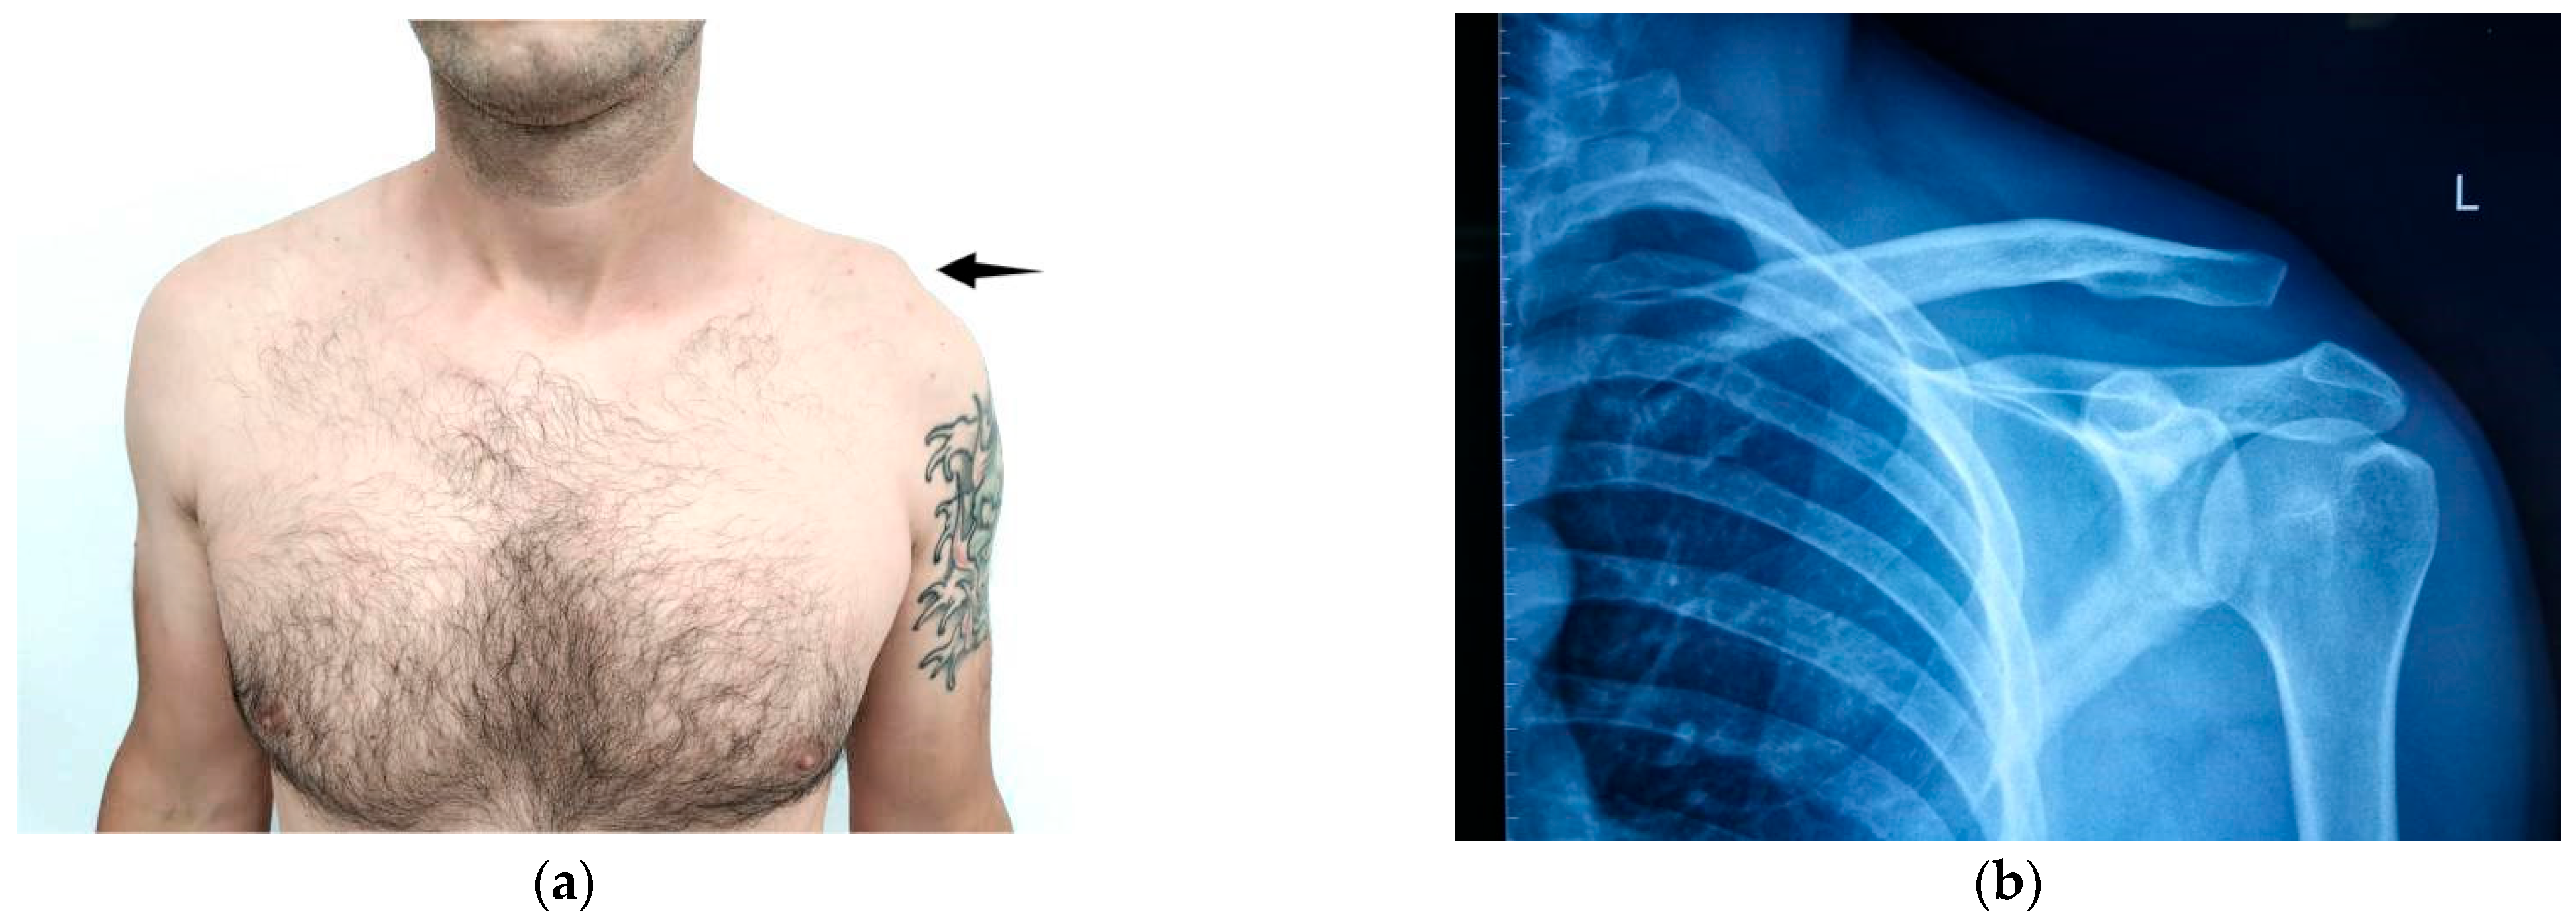

Diagnosis of AC joint injuries is primarily based on clinical examination and radiographic evaluation. Patients typically report pain localized to the AC joint, which worsens with cross-body movements but can be alleviated with local anesthesia [9]. A visible elevation of the clavicle may be observed, which is temporarily reducible with downward pressure, a phenomenon known as the “piano key sign” (Figure 1).

Figure 1. (a) Clinical aspect and (b) X-ray image of left AC separation.